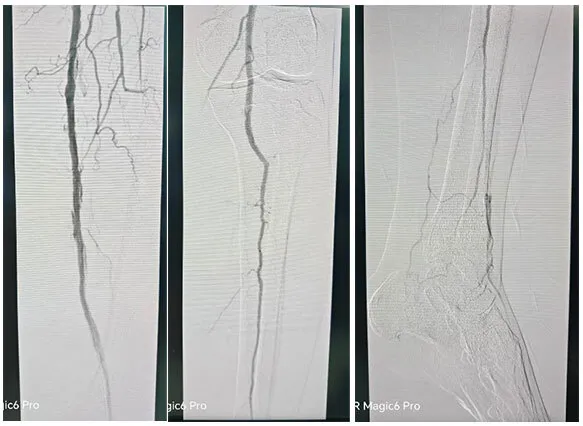

主诉åQ?/strong>åŒä¸‹è‚¢é—´æ­‡æ€§è·›è¡?òq?加é‡3月余ã€?/p>

术å‰è¯Šæ–­åQšå¤–院CTA½CÞZ¸‹è‚¢åŠ¨è„‰ç¡¬åŒ–é—­å¡žç—‡,åŒä¾§è†ä¸‹åŠ¨è„‰å¤šå‘多支下肢动脉闭塞ã€?/p>

手术˜q‡ç¨‹åQ?/strong>å¯ég¸å¯¼ç®¡é…åˆå»ºç«‹é€šèµ\åŽï¼Œä½¿ç”¨2.5*150mmã€?*120mmçƒå›Šæ‰©å¼ èƒ«åŽåŠ¨è„‰ç‹­çª„ŒDµï¼Œä½¿ç”¨2*80mmã€?.5*150mmçƒå›Šæ‰©å¼ è…“动脉狭½H„段åQŒé¢„扩åŽä½¿ç”¨¾U¦æŸåž‹è¯ç‰©çƒå›?*120mmã€?*150mm分别扩张胫åŽåŠ¨è„‰ã€è…“åŠ¨è„‰ã€‚å¤æŸ¥é€ åª„½Cºå†…膜光滑,无造媄剂外渗,è†ä¸‹˜qœç«¯åŠ¨è„‰ä¸¤æ”¯æ˜‘Öª„è‰¯å¥½ã€‚æ‰‹æœ¯é¡ºåˆ©ï¼Œæœ¯åŽæ‚£è€…安˜q”ç—…æˆÑ€?/p>

03 病例�/strong>

主诉åQ?/strong>åŒä¸‹è‚¢åŠ¨è„‰é—­å¡?月余åQŒå·¦ä¸‹è‚¢æœ¯åŽ3周余ã€?/p>

术å‰è¯Šæ–­åQ?/strong>下肢CTA½CºåŒä¸‹è‚¢åŠ¨è„‰å¤šå‘æ··åˆæ–‘å—åQŒç®¡è…”轻中度狭窄åQŒå·¦ä¾§è‚¡æ·±åŠ¨è„‰å¤šå‘æØœåˆæ–‘å—,½Ž¡è…”局部闭塞ã€?/p>

手术˜q‡ç¨‹åQ?/strong>å¯ég¸å¯¼ç®¡é…åˆå»ºç«‹é€šèµ\åŽï¼Œä¿æŠ¤ä¼žä¸‹ä½¿ç”¨4*150mmçƒå›Šé¢„扩张病å˜ï¼Œåˆ†åˆ«äº¤æ¢5*200mm¾U¦æŸåž‹è¯ç‰©çƒå›Šæ‰©å¼ é—­å¡žæ®µåŠè‚¡‹¹…动脉上ŒD늋­½H„处åQ?*150mm¾U¦æŸåž‹è¯ç‰©çƒå›Šæ‰©å¼ èƒ«è…“干开å£ä¸ŠŒDµï¼Œéž˜å†…造媄昄¡¤ºè‚¡æµ…å¼€å£å¤„有残余狭½H„,余闭塞段完全å¤é€šï¼Œå†…膜光整åQŒè¡€‹¹é€šç•…åQŒå¼•å…¥DES6*40m支架一枚予以股‹¹…å¼€å£å¤„释放åQŒå¤æŸ¥é€ åª„æç¤ºç‹­çª„解除åQŒæœªè§é€ åª„剂外渗,è†ä¸‹˜qœç«¯åŠ¨è„‰å„分支显å½Þp‰¯å¥½ï¼Œæœªè§æ˜Žæ˜¾æ “å¡žã€‚æ‰‹æœ¯é¡ºåˆ©ï¼Œæœ¯åŽæ‚£è€…安˜q”ç—…æˆÑ€?/p>